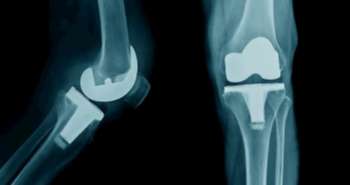

Evaluation of bone mineral density (BMD) is an essential factor for estimating fractures of the femoral neck, as per the analysis published in the Journal, PM & R. The subjects with the long-term residual lower extremity (LE) weakness after polio exhibited reduced BMD, linked with the weakness of muscles.

This retrospective study assessed whether the BMD of femoral neck varied from side to side among people with asymmetrical LE muscle infirmity along with the persons who were at risk for under diagnosis of low BMD, as the low BMD or osteoporosis diagnosis significantly associated with the unilateral evaluation of the femoral neck. The patients selected for the analysis were of >18 years old with full appropriate information. The side of LE weakness (strength score), BDt T scores, and BMD divisions based on standard T-score limits were taken as the major study outcomes.

A total of 43 individuals found to have at least one bilateral LE strength and femoral neck T scores. Fourteen subjects exhibited BDt on their stronger LE and 14 (32.5%) on their stronger LE. Further, the T scores noticed to be higher in stronger LE than the weaker LE. Analysis of osteoporosis or low bone density or was more common based on T scores have chosen on a weaker LE than a stronger LE.

Therefore, in the little sample, using strong-limb T scores ended in fewer people described as having osteoporosis or low bone density than when weak-limb T scores were used. Depreciating BMD loss may involve inadequate treatment and enhanced risk of mortality, morbidity, and costs linked with osteoporosis of femoral neck in this high-fall-risk class. This implies a significant association of BMD and femoral neck fractures.